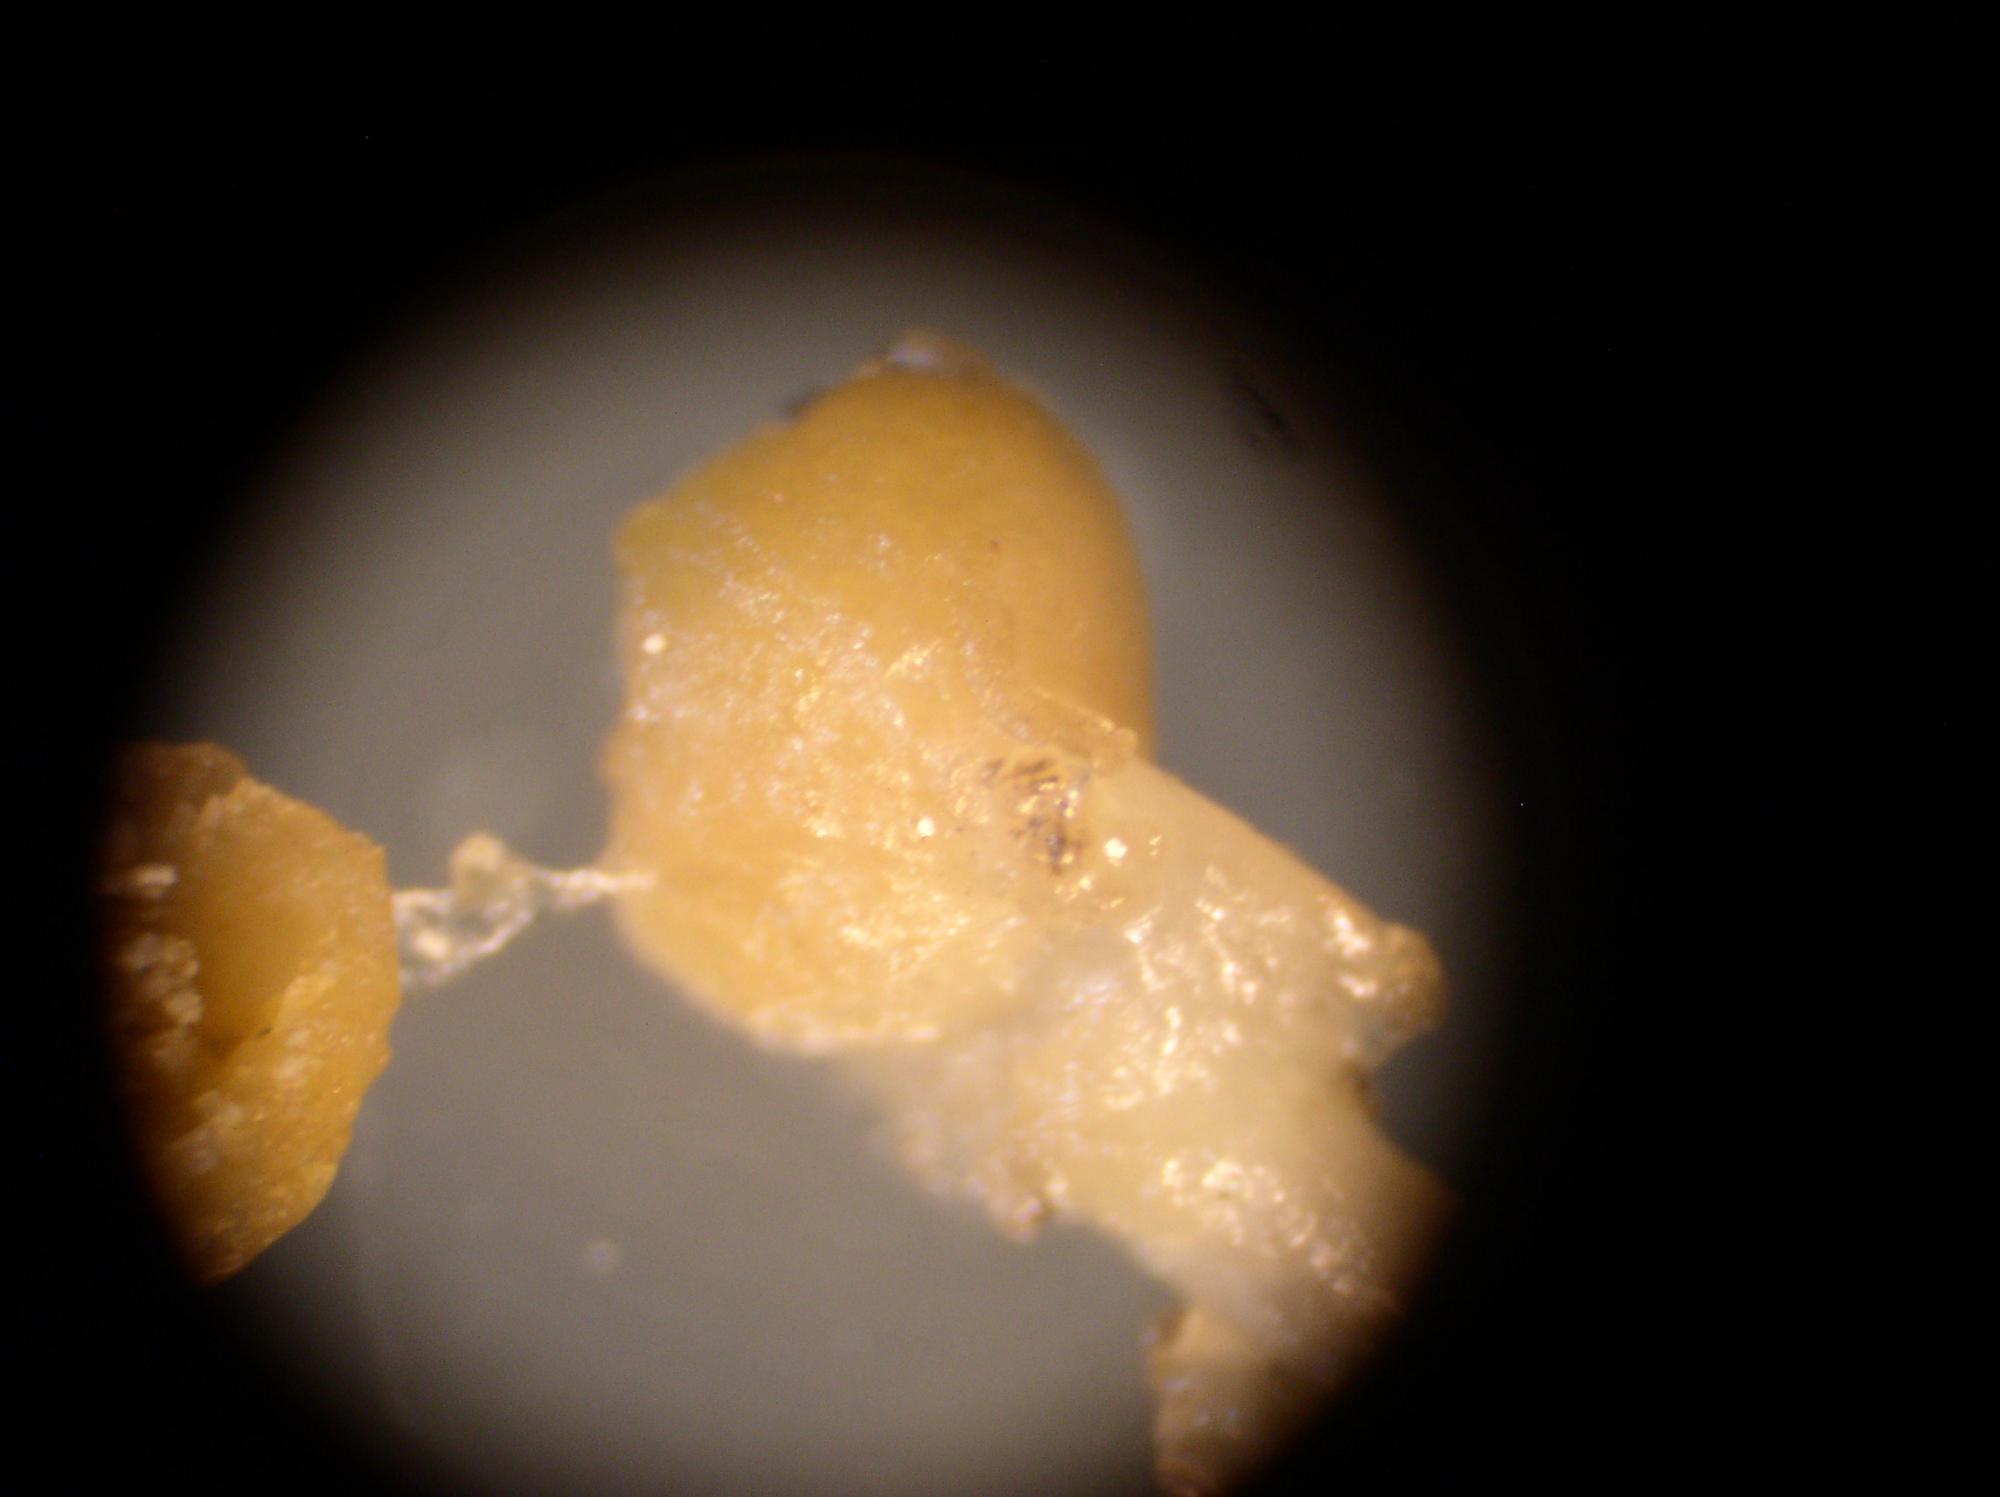

Вот фото, которые удалось сделать дома.

Сейчас иду в лабораторию.

На фото:

1,2,6 - целые капсулы.

Они блестящие, покрыты некой плёнкой.

3-5 - разрезанные капсулы.

Внутренняя структура нопоминает мокрый хлебный мякиш.

В этом "мякише видны чёрные включения, как кусочки грязи.

7,8 - кожа возле жабер.

На коже видны участки без кожи.

9,10 - внутренние органы.

Справа вверху видна капсула.

Она там и была.

И видны чёрные сеточки.

11 - общий вид.

Видны многочисленные капсулы.

больше похоже на жировики. При большем увеличении не микроскопировали?